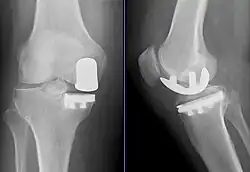

Radiographs of a knee arthroplasty of the medial compartment | |